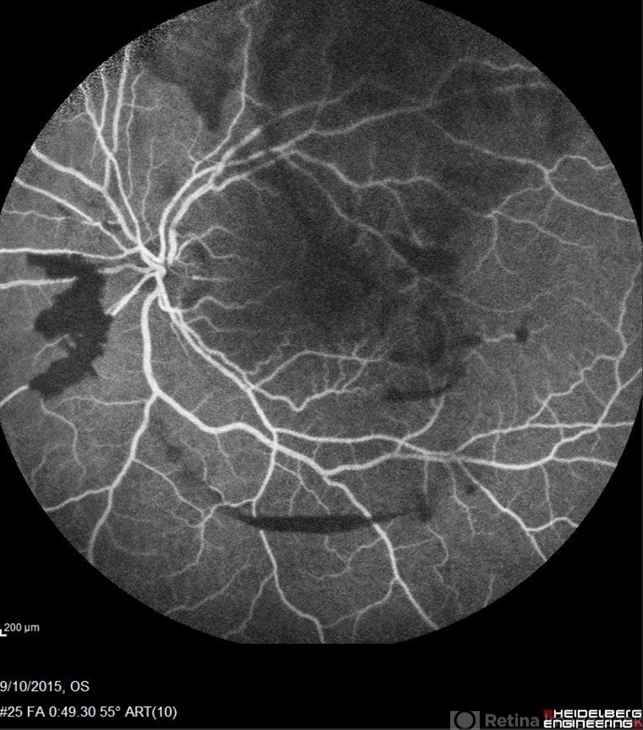

- Sickle Cell Retinopathy

- sickle cell retinopathy, peripheral retinal neovascularization, sea fan

- Scanning laser ophthalmoscope

- Angiography showed normal vessels posteriorly but severe capillary drop out throughout the periphery OU with scattered severe neovascularization at the edge of the capillary drop out peripherally. Note the preretinal and vitreous hemorrhage obscuring the view of the retinal vasculature.